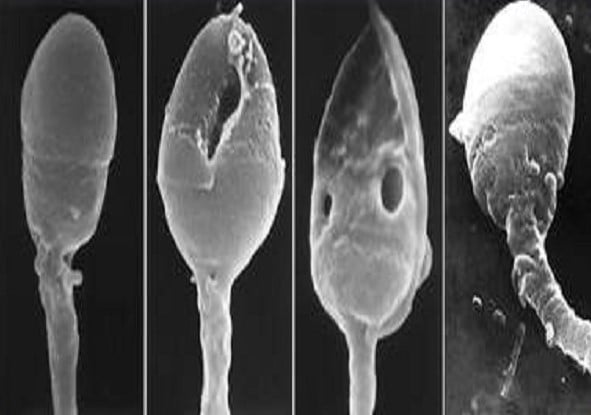

ИМСИ — это изучение и отбор сперматозоидов под большим оптическим увеличение, которое порой достигает до 6 тысяч раз. Именно при таком увеличении можно увидеть все возможные дефекты у сперматозоидов. При оплодотворении ИКСИ оптическое увеличение происходит с размеров в 400 раз, что не дает возможности детального изучения строения сперматозоида.

Отбор сперматозоидов

Ученые доказали, что если оплодотворить яйцеклетку женщины при помощи ИКСИ дефектным сперматозоидом, то развитие будет происходить до определенного момента, потом же эмбрион деградирует или не имплантируется вообще. Именно поэтому главной задачей программы ИКСИ ИМСИ, является отбор сперматозоидов без дефектов, которые могут приводить к аномальному развитию плода и выкидышам. К таким аномалиям могут привести дефекты головы сперматозоида, к примеру, различные включения и пузырьки. Это можно увидеть лишь под большим оптическим увеличением, применяемом для диагностики ИМСИ.